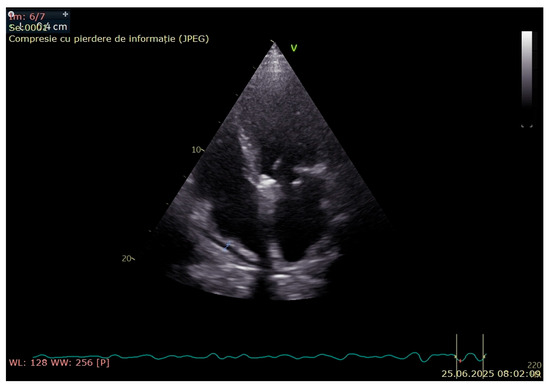

3. Case Presentation